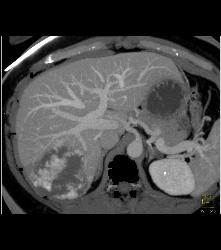

Hemangioma in A Full Sequence of Phases